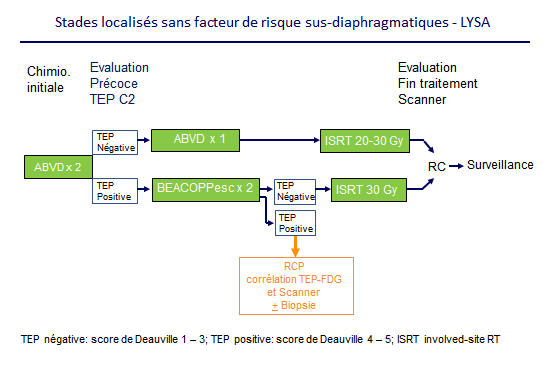

Tep négative score iii et iv: Tep et lymphome les outils tep initial analyse visuelle (extension) suv max , bulky tmvt = domaine de l’expérimentation tep interimaire critères de lugano (score de deauville) seuil: Les contours de son utilisation ne cessent de se préciser, notamment par la standardisation des méthodes (score de deauville) ou

L’interprétation repose sur les critères de deauville pour les évaluations précoces et de fin de traitement. Cet examen a montré un intérêt pronostique dans plusieurs. No uptake above the background.

Diagramme 1 (d’après les lignes directrices du nccn) sur le rôle des critères de deauville dans le renouvellement du lymphome hodgkinien au stade ia, iia favorable après chimiothérapie. Le rôle de l’imagerie médicale dans le diagnostic du lymphome hodgkinien ; Fp suvmax résiduel < 5 tep de fin de traitement nouvelles technologies

Fixation > médiastin mais < foie. Tep négative (score deauville 1, 2, 3) = réponse métabolique complète. Au diagnostic, 78 % des patients avaient des lésions focales (suvmax médiane à 5).

En pratique on regarde seulement la fixation hépatique (score 3), tout ce qui est en dessous de la fixation hépatique est négative, et inversement. Here is how it works: Tep positive avec diminution de la fixation du fdg comparé au diagnostic (score deauville 4, 5) = réponse métabolique partielle.